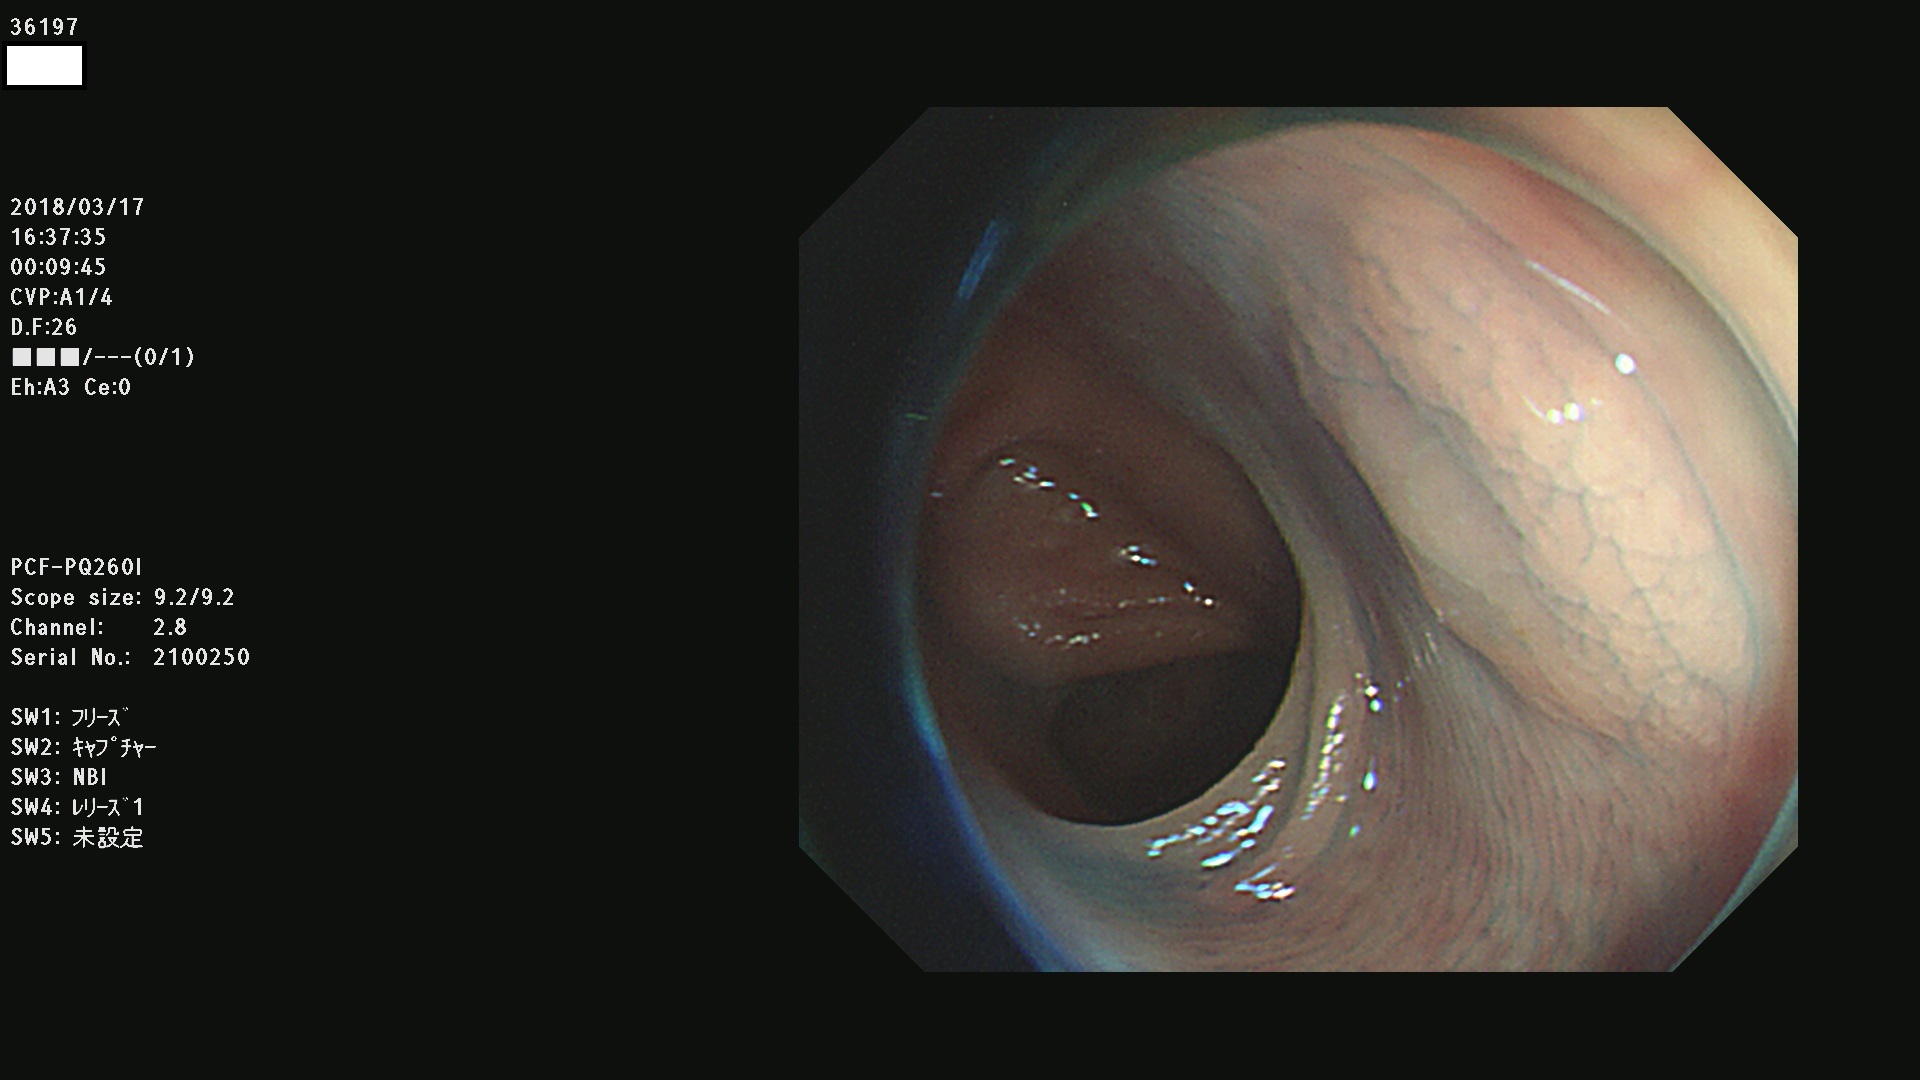

腺腫発見率57 % (カルテ番号 36100〜36199の100名の方の検査結果で集計)大腸癌検診最新情報

以下のカルテ番号の方に腺腫(Adenoma,Group3〜5)が見つかりました(集計法)

36100 36101 36102 36103 36104 36105 36107 36108 36110 36111 36114 36115 36117 36119 36120 36122 36125 36127 36129(SSA/Pのみ) 36133 36135 36137 36138 36139 36143 36144 36146 36147 36152 36153 36154 36155 36157(SSA/Pのみ) 36158 36162 36163 36165 36167 36169 36170 36173 36174 36176 36177 36178 36179 36180 36183 36185 36187 36189 36190(SSA/Pのみ) 36191 36193 36195(SSA/Pのみ) 36197(SSA/Pのみ) 36199(SSA/Pのみ)

発見困難で危険性の高い平坦型病変(上記100名より抽出) ![]()